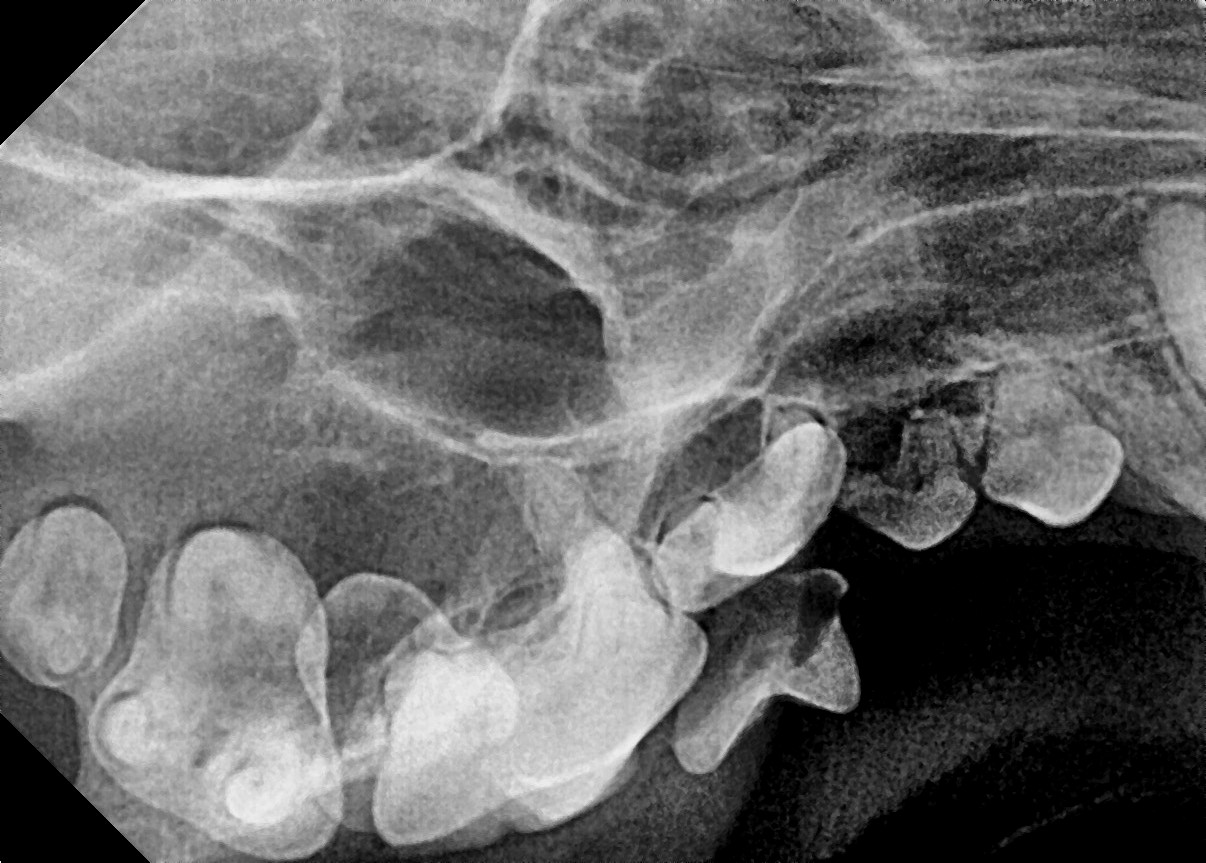

다음은 본원에 내원하여 잔존 유치를 발치한 사례입니다.

이번 사례는 송곳니 유치가 제때 빠지지 않았을 때 생길 수 있는 문제와 그 해결방법에 대하여 말씀드리고자 합니다.

잔존 유치가 탈락되지 않아 영구치가 치아 사이에 같혀 있음 위 사진은 유치가 제때 탈락되지 않아 영구치가 세 번째 앞니 아래에 갇혀 있는 것을 보여줍니다.

세 번째 앞니도 송곳니 간섭으로 인해 정상위치 보다 위쪽으로 벗어나 있는 것(deviation)을 확인할 수 있습니다.

잔존 유치를 제거해 주었더니 별다른 교정 장치를 사용하지 않았음에도 2주 후 제위치로 이동하고 있는 송곳니를 확인할 수 있습니다.